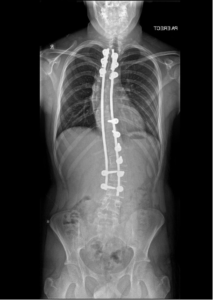

The traditional medical approach to scoliosis is to watch and monitor it if under 20 degrees. From 20 degrees upwards to 40 or 50 degrees a brace may be recommended to be worn for 12-20 hours per day with or without some physiotherapy. This is done to theoretically keep the spine from continuing to progress into a more severe curve, not necessarily correct the curve that’s already there. Once the spine gets to a curve of 40 degrees or above, your surgeon may make a recommendation for surgery. Most common surgical option is where metal screws are drilled into your individual vertebrae and then tied to metal rods which are placed along both sides of the spine. The bones are then pulled together to reduce the curvature and bone grafts are placed in between the bones in order to attempt fusing all the affected segments together.

Although it can improve the angles of the curve itself, this type of treatment does have some downsides besides just the invasive surgery and scars left afterwards. Metal rods and screws are generally left in the body and the fused segments don’t move. When joints don’t move they tend to degenerate faster than they would if they had movement. Then the “still moving” segments of the spine have to work harder to compensate for the immobility of the fused segments. Long story short, the bones, discs, muscles, and nerves aren’t always happy post-op or a few years later.

Case courtesy of Jeremy Jones, Radiopaedia.org. From the case rID: 89552